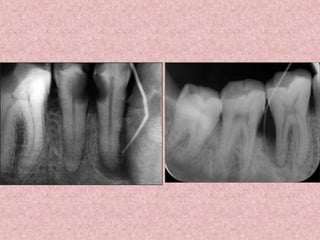

(a) Perforation of the pulpal floor of the mandibular first molar occurred in conjunction

with a search for root canal openings. There is also a file fragment in one of the mesial

canals.

(b) The perforation was immediately sealed with guttapercha.

(c) In a radiograph taken 1 month after treatment a slight radiolucency is seen at the

site of the perforation (arrow).

(d) Follow-up after 2 years showed normal periodontal conditions both clinically

and radiographically